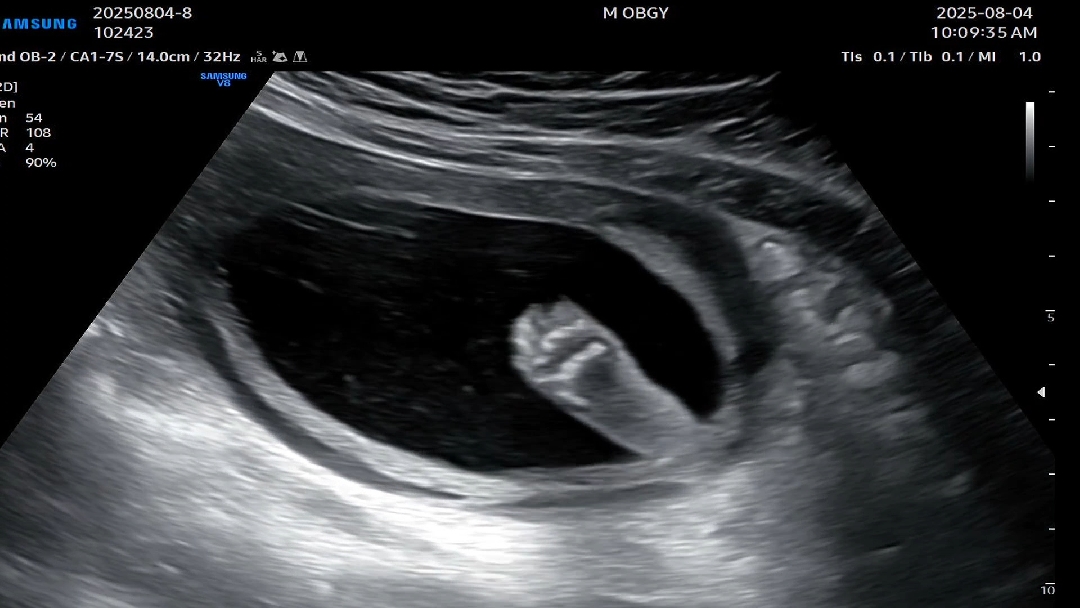

귀여운 발 보고가세요

오늘 20주0일 꿀떡이 보고왔어요 주수내에서 쪼오오오금 큰편인뎈ㅋ 커봣자 얼마나 크냐구요 ㅋㅋㅋ 발바닥 보고 심쿵 당하고 왔습니다♡♡♡